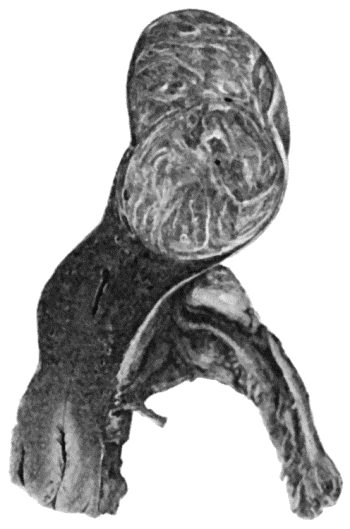

| 135. | Cadaver, illustrating the alterations in the Lower Limbs resulting from Ostitis Deformans | 475 |